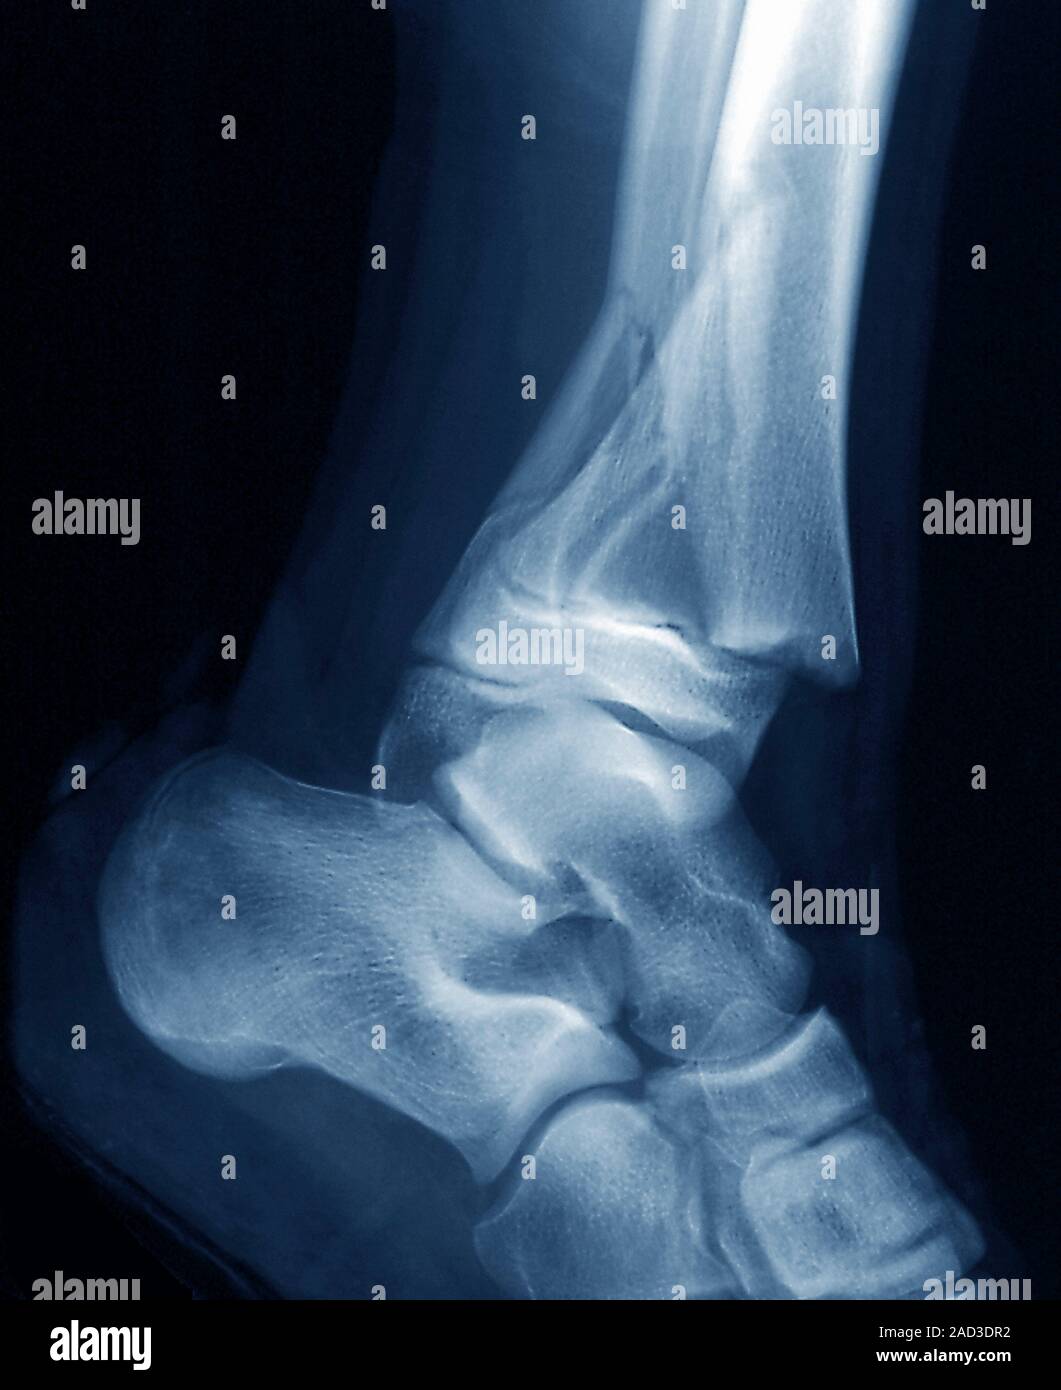

From www.alamy.com

Coloured Xrays of the pinned ankle of a 32 year old male patient. A Calf In Bone Fracture A broken leg (leg fracture) is a break or crack in one of the bones in your leg. Fibula fractures occur around the ankle, knee, and middle of the leg. There are different types of fractures, which can also affect treatment and recovery. If you have a displaced fracture, the care. Common causes include falls, motor vehicle accidents. A broken. Calf In Bone Fracture.